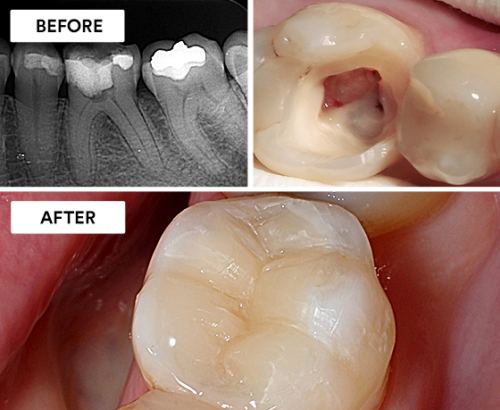

Root Canal Treatment (RCT) is a dental procedure to treat infections or damage within a tooth’s pulp, which contains nerves and blood vessels. The process involves removing the infected or damaged pulp, cleaning the canal, and sealing it to prevent further infection. After cleaning, the tooth is often restored with a crown to ensure strength and functionality. RCT alleviates pain, preserves the natural tooth, and prevents the spread of infection. While notorious for being associated with discomfort, modern techniques and anesthesia make root canal treatments relatively painless, providing an essential option to save a tooth and maintain oral health. Regular follow-ups ensure long-term success.

- Pulp removal and cleaning: Infected or damaged pulp is removed, and the root canals are thoroughly cleaned and disinfected.

- Filling and restoration: The cleaned canals are filled with a sealing material, and a temporary filling or crown is placed initially, followed by a permanent restoration to protect and strengthen the treated tooth.